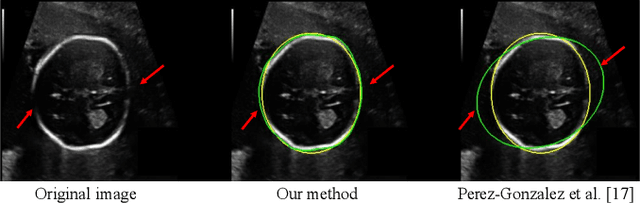

Despite that deep learning has achieved state-of-the-art performance for medical image segmentation, its success relies on a large set of manually annotated images for training that are expensive to acquire. In this paper, we propose an annotation-efficient learning framework for segmentation tasks that avoids annotations of training images, where we use an improved Cycle-Consistent Generative Adversarial Network (GAN) to learn from a set of unpaired medical images and auxiliary masks obtained either from a shape model or public datasets. We first use the GAN to generate pseudo labels for our training images under the implicit high-level shape constraint represented by a Variational Auto-encoder (VAE)-based discriminator with the help of the auxiliary masks, and build a Discriminator-guided Generator Channel Calibration (DGCC) module which employs our discriminator's feedback to calibrate the generator for better pseudo labels. To learn from the pseudo labels that are noisy, we further introduce a noise-robust iterative learning method using noise-weighted Dice loss. We validated our framework with two situations: objects with a simple shape model like optic disc in fundus images and fetal head in ultrasound images, and complex structures like lung in X-Ray images and liver in CT images. Experimental results demonstrated that 1) Our VAE-based discriminator and DGCC module help to obtain high-quality pseudo labels. 2) Our proposed noise-robust learning method can effectively overcome the effect of noisy pseudo labels. 3) The segmentation performance of our method without using annotations of training images is close or even comparable to that of learning from human annotations.